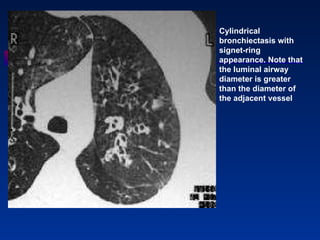

Cylindrical bronchiectasis with signet-ring appearance. Note that the luminal airway diameter is greater than the diameter of the adjacent vessel

Cylindrical bronchiectasis withsignet-ring appearance. Note that the luminal airway diameter is greater than the diameter of the adjacent vessel